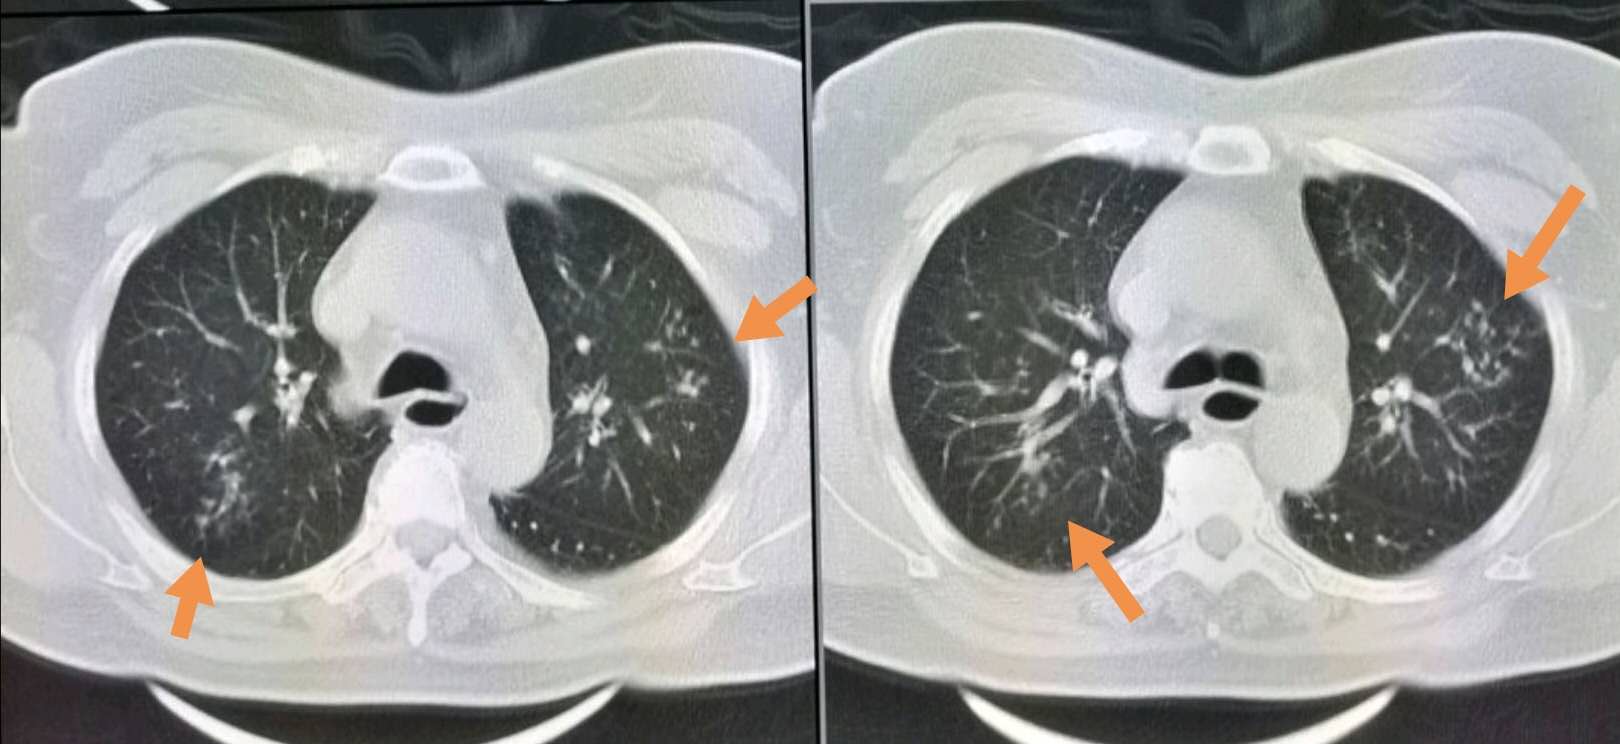

像这位62岁的小老太,就是食管反流引起的反复咳嗽、喘憋、发热,胸部CT发现双侧多发的小炎症,都沿着支气管分布。

两年里住院3回了。

上面那位老太太经过饮食调理和药物治疗,二次复查时肺部病灶已经明显吸收:

相信她经过这种针对性治疗,以后就不必反复住院了。